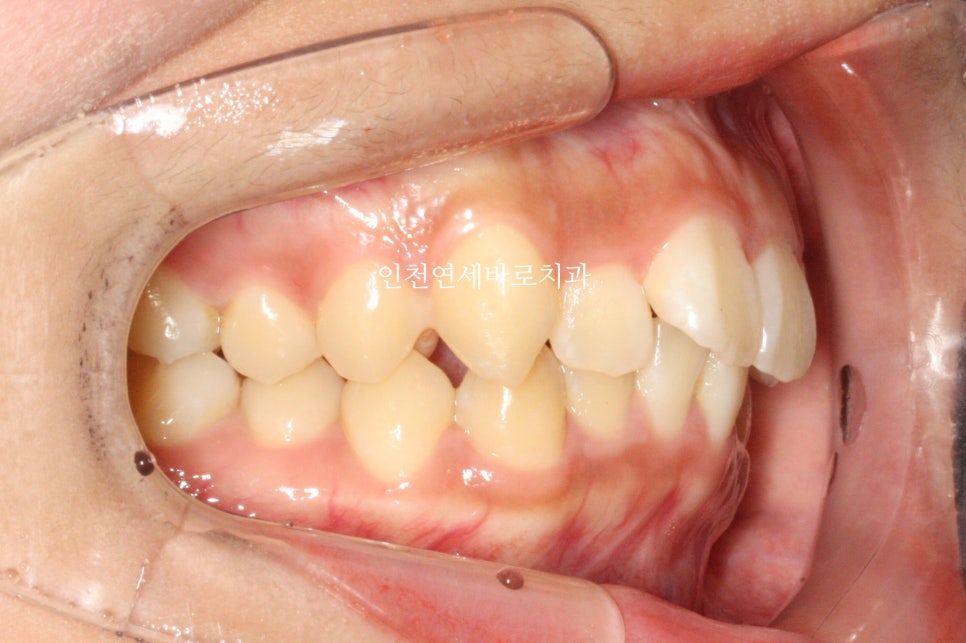

위아래 덧니가 있었고, 깊이 물리는 과개교합 및 중심선의 불일치 보이고 있습니다.

덧니를 비발치로 해결하면서 입술도 후방이동하기로 했습니다.

비발치로 진행 시 입술이 안들어간다, 오히려 더 나온다. 이런말들이 많은데 항상 옳지 않습니다.

골격에 대한 분석 후 위쪽 치열은 후방 + 상방 으로 당겼습니다.